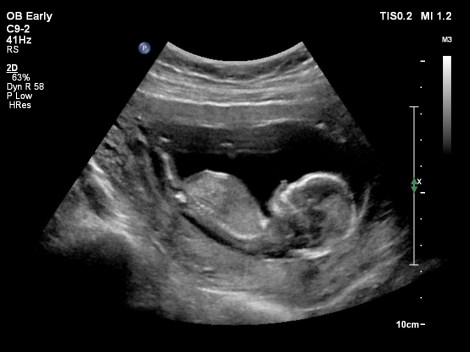

Jullie lezen het goed! Er is een nieuwe rubriek bij op BiologischNatuurlijk, Bio&Baby. Wij verwachten namelijk rond de zomer vader en moeder te worden van ons eerste kindje.